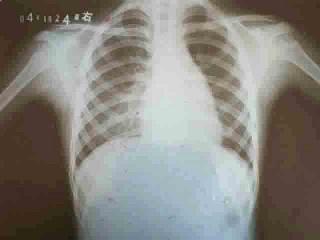

11个月婴儿,突然起病,持续高热5天,频繁咳嗽,喘憋。听诊右下肺呼吸音减弱,偶可闻及少许湿性啰音,叩诊浊音,白细胞6×10/L。胸片示右下肺小片状影,见图...

问题 11个月婴儿,突然起病,持续高热5天,频繁咳嗽,喘憋。听诊右下肺呼吸音减弱,偶可闻及少许湿性啰音,叩诊浊音,白细胞6×10/L。胸片示右下肺小片状影,见图。最可能的诊断是 ( )

选项 A、腺病毒性肺炎 B、支原体肺炎 C、金黄色葡萄球菌肺炎 D、吸人性肺炎 E、急性毛细支气管炎

答案 A